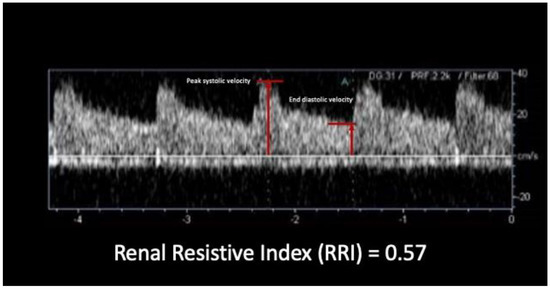

- Samoni, S.; Nalesso, F.; Meola, M.; Villa, G.; De Cal, M.; De Rosa, S.; Petrucci, I.; Brendolan, A.; Rosner, M.H.; Ronco, C. Intra-Parenchymal Renal Resistive Index Variation (IRRIV) Describes Renal Functional Reserve (RFR): Pilot Study in Healthy Volunteers. Front. Physiol. 2016, 7, 286. [Google Scholar] [CrossRef]

- Samoni, S.; Villa, G.; De Rosa, S.; Husain-Syed, F.; Guglielmetti, G.; Tofani, L.; De Cal, M.; Nalesso, F.; Meola, M.; Ronco, C. Ultrasonographic Intraparenchymal Renal Resistive Index Variation for Assessing Renal Functional Reserve in Patients Scheduled for Cardiac Surgery: A Pilot Study. Blood Purif. 2022, 51, 147–154. [Google Scholar] [CrossRef]

- Tublin, M.E.; Bude, R.O.; Platt, J.F. Review. The resistive index in renal Doppler sonography: Where do we stand? AJR Am. J. Roentgenol. 2003, 180, 885–892. [Google Scholar] [CrossRef]